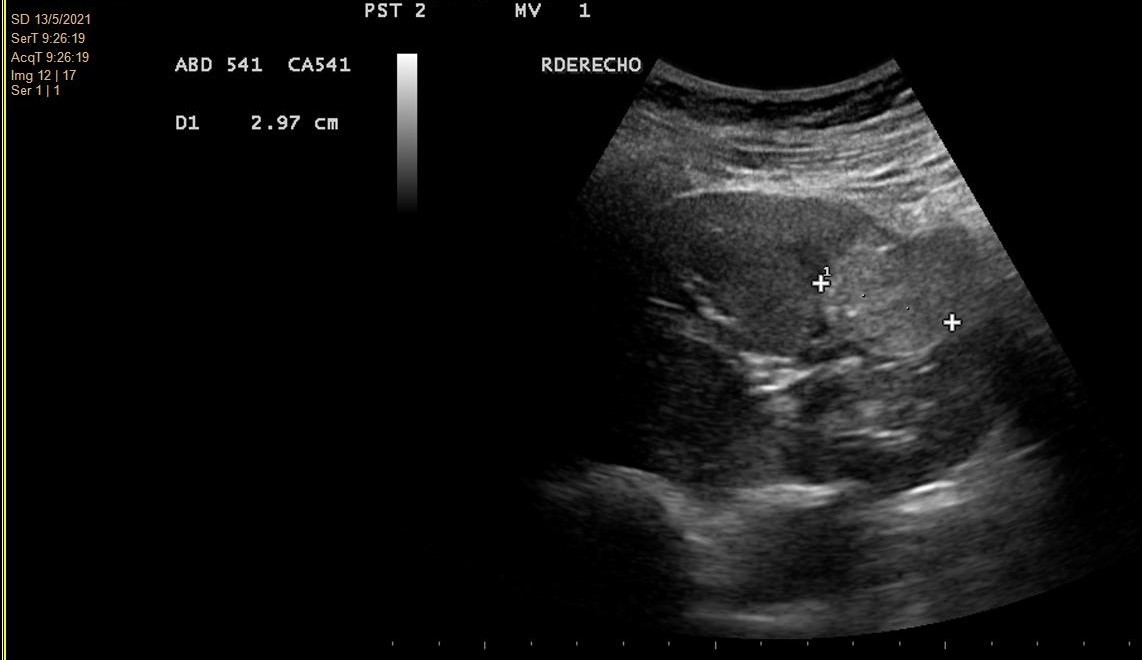

- Hallazgos ecográficos (mayo 2021): Imagen hiperecogénica redondeada de 2,9 cm de diámetro, de ecogenicidad irregular, localizada en tercio medio-distal del riñón derecho, sin evidenciarse litiasis o hidronefrosis.